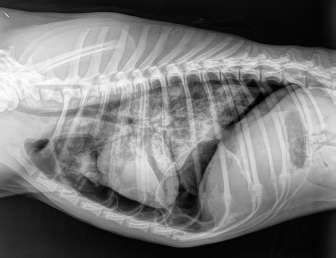

Case details for each of the five dogs included in the study are listed in Table 1. The etiology of the pneumothorax were congenital pulmonary bullae in two dogs, traumatic in one (road traffic accident), lungworm infection in one, and unknown in the remaining dog. Dog number 1 presented a large pulmonary bulla in the right cranial pulmonary lobe (Fig. 1). Dog number 2 presented four bullae: two in the medial aspect of the left cranial lung lobe (17 mm each), one in the caudal aspect of the left caudal lung lobe (26 mm), and another in the caudal border of the left caudal lung lobe (36 mm) (Fig. 2). Dog number 3 presented a large bulla measuring 33 mm in the medial aspect of the right middle lung lobe and around 10 blebs measuring from 3 to 6 mm in the ventral border of both right and left cranial lung lobes. Dog number 4 developed multiple small bullae and a larger one measuring over 10 cm, 24 hours after treatment of lungworm with spot on Imidacloprid and Moxidectin, which were responsible for a moderate unilateral pneumothorax (Fig. 3). Despite the severity of the pneumothorax, dog number 5 did not show any lesions on the computed tomography (CT) scan that could clearly explain its origin. Only one chest tube was placed in dogs 1, 2, 3, and 4. Two were placed in dog 5.

Fig. 3. Right-lateral thoracic radiograph of a 9-month-old female dog (dog number 4) suffering from a pneumothorax secondary to lungworm infection.